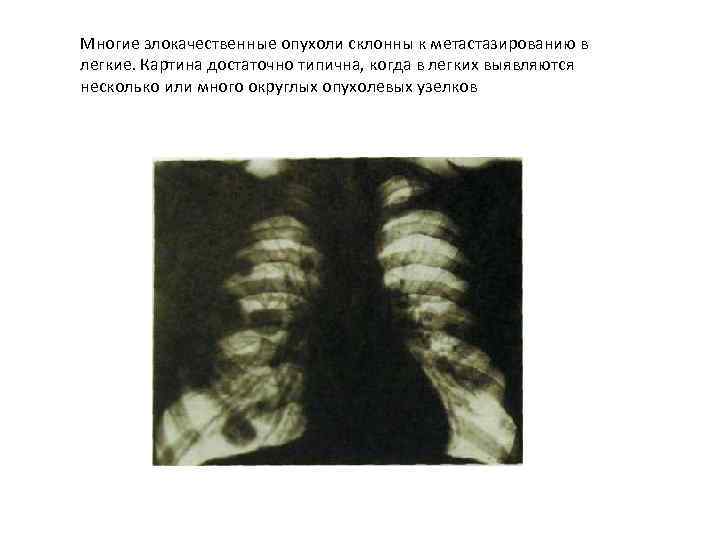

Многие злокачественные опухоли склонны к метастазированию в легкие. Картина достаточно типична, когда в легких выявляются несколько или много округлых опухолевых узелков

Многие злокачественные опухоли склонны к метастазированию в легкие. Картина достаточно типична, когда в легких выявляются несколько или много округлых опухолевых узелков